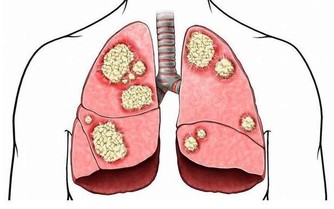

肝臟是貯存維生素和礦物質的重要臟器,而隨著肝臟脂肪增加,可導致貯存營養素的能力降低,如不注意補充,可引發營養素缺乏。而某些維生素和礦物質的缺乏反可加劇肝臟脂肪蓄積,甚至引發肝髒病變。

如維生素C可促進氨基酸中酪氨酸和色氨酸的代謝,促進載脂蛋白合成而有助排出肝臟脂肪。硒是一種強抗氧化劑,具有保護肝細胞結構完整、清除自由基、加快脂質過氧化物分解的作用。因此,脂肪肝的糖友在平衡膳食的基礎上,應常食富含維生素C的深色蔬菜及富含硒的海產品。